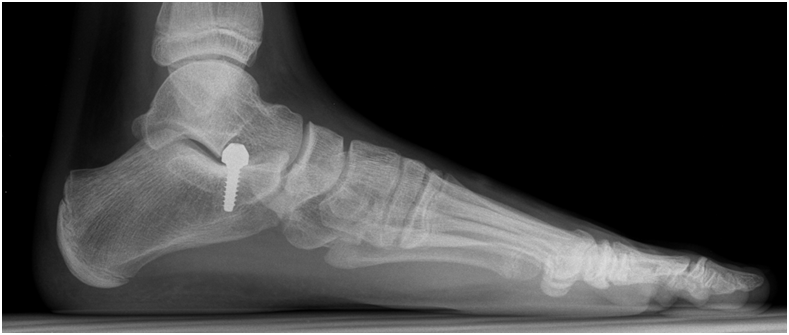

The medical team had two-hour surgery to adjust the heel with screws and prune down the tendon using a dissolving screw.

The operation ended successfully, and the patient left the hospital in good health. This intervention is considered the first-ever in the field of orthopedy.